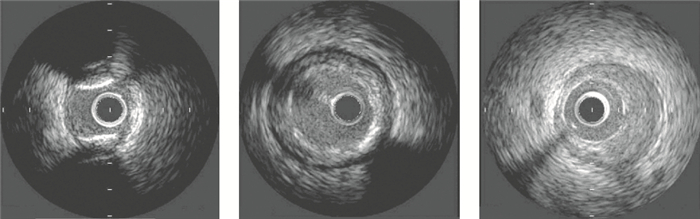

如圖 1所示,在異常IVUS圖像中,依據成分可將斑塊組織分為四類[4]:①脂質斑塊,透聲性強,表現為低回聲區;②纖維斑塊,回聲強度與鈣化性斑塊相近,但其后無負性聲影;③鈣化斑塊,回聲很強,強回聲后有負性聲影;④混合性斑塊,同時具有兩種或以上上述斑塊的聲學特征。由于超聲顯像自身的局限性,目前僅根據IVUS灰階圖像尚難以嚴格區分混合性斑塊[19]。因此,本文僅對鈣化、纖維化和脂質斑塊進行識別。